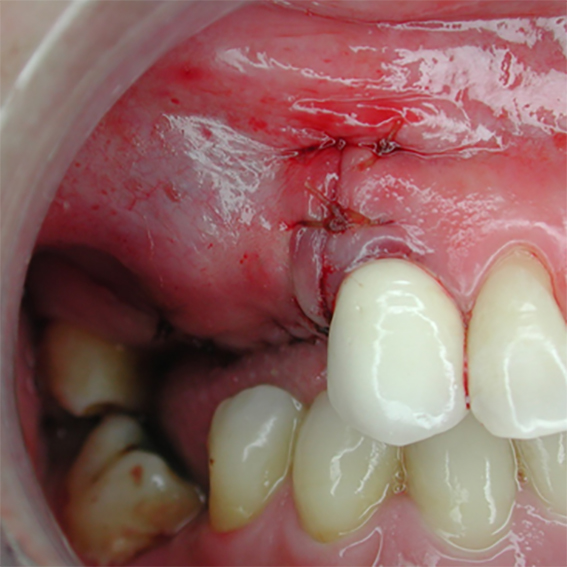

Pure titanium membrane of ultra-thin thickness of about 10 microns (0.01mm). Totally inert, biocompatible and non-biological thus removing the fear of disease transmission from collagen of bovine source. It allows ease of handling and adaptation over the operative site. Because of its mouldability, it does not require pin or screw fixation, thus avoiding the risks of pin or screw swallowing or aspiration. Excellent clinical performance in guided tissue regeneration. Resistance to infection after exposure. Primary wound closure is not necessary. No tissue reaction or wound infection.